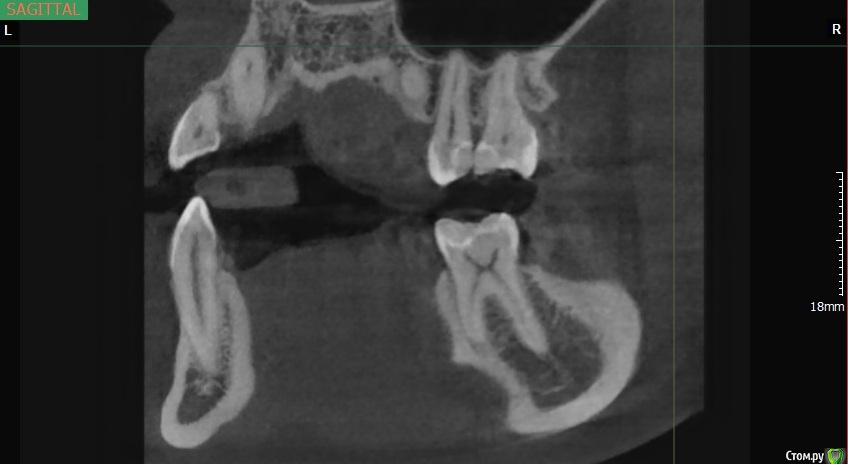

Fatality Опубликовано 12 июня, 2017 Поделиться Опубликовано 12 июня, 2017 Здравствуйте! Возникло 2 вопроса после лечения зубов.Первый вопрос касается зуба 4.6. После чистки камней появилась боль при накусывании на 4.6, при лечении был выявлен глубокий кариес. Зуб почистили, закрыли пломбой, но болевые ощущения уже 2 недели при накусывании не уменьшаются и не уходят (в спокойном состоянии зуб не беспокоит). Прилагаю снимок после лечения (сделан как раз к концу 2й недели), чтобы понять - стоит ли ждать, что неприятные ощущения пройдут или же нужно заново вскрывать и что-то с этим делать. Если нужно покрутить зуб в разных плоскостях, могу сделать и прислать дополнительные фотографии.И второй вопрос касательно пор в пломбировочном материале. Последние несколько месяцев по рекомендации знакомых ходила к одному и тому же стоматологу, и вроде бы все устраивало, но сделала КТ и при расшифровке мне указали на поры в пломбах во всех зубах, которые лечил этот врач (снимок прилагаю, мне обвели красным как раз одну из пор). Объясните, пожалуйста: в чем опасность пор, стоит ли перелечивать эти зубы заново (период, за который они были сделаны - с декабря 2016 по май 2017), и нужно ли менять стоматолога раз такая ситуация повторилась на всех зубах, которые он делал. Ссылка на комментарий

St. Опубликовано 12 июня, 2017 Поделиться Опубликовано 12 июня, 2017 А кто Вам КТ расшифрововал?По приложенному скрину проблем с пломбами не увидела, то что вы приняли за пору наложение в проекции.В нижнем зубе пломба достаточно близко к нерву. По высоте она вам не мешает? Ссылка на комментарий

St. Опубликовано 12 июня, 2017 Поделиться Опубликовано 12 июня, 2017 Возможно в какой-то точке пломба не до конца приклеилась, иногда такое бывает, поэтому болит. Обратитесь с этим к своему доктору, опишите ощущения. скорее всего доктор предложит заменить пломбу на условно временную из стеклоиономера и понаблюдать. в большинстве случаев это помогает. Если же ощущения не пройдут возможно придется убирать из зуба "нерв". Ссылка на комментарий

DmitrySH Опубликовано 12 июня, 2017 Поделиться Опубликовано 12 июня, 2017 Поры в пломбировочном материале, так же как и нарушение прилегания пломбировочного материала на КТ точно диагносцировать не представляется возможным из-за особенностей КТ. На прицельных снимках будет видно. Ссылка на комментарий

DmitrySH Опубликовано 13 июня, 2017 Поделиться Опубликовано 13 июня, 2017 На последок хотелось бы уточнить: моя первостепенная задача в настоящее время - настоять на прицельном снимке 46, чтобы врач обратил внимание на целостность и плотность прилегания пломбы к зубу + не торопиться дергать нервы, а попробовать сохранить то что есть путем установки временной пломбы? Да, или сразу постоянную сделать. Если объективно ничего особенного не выявится. Ссылка на комментарий